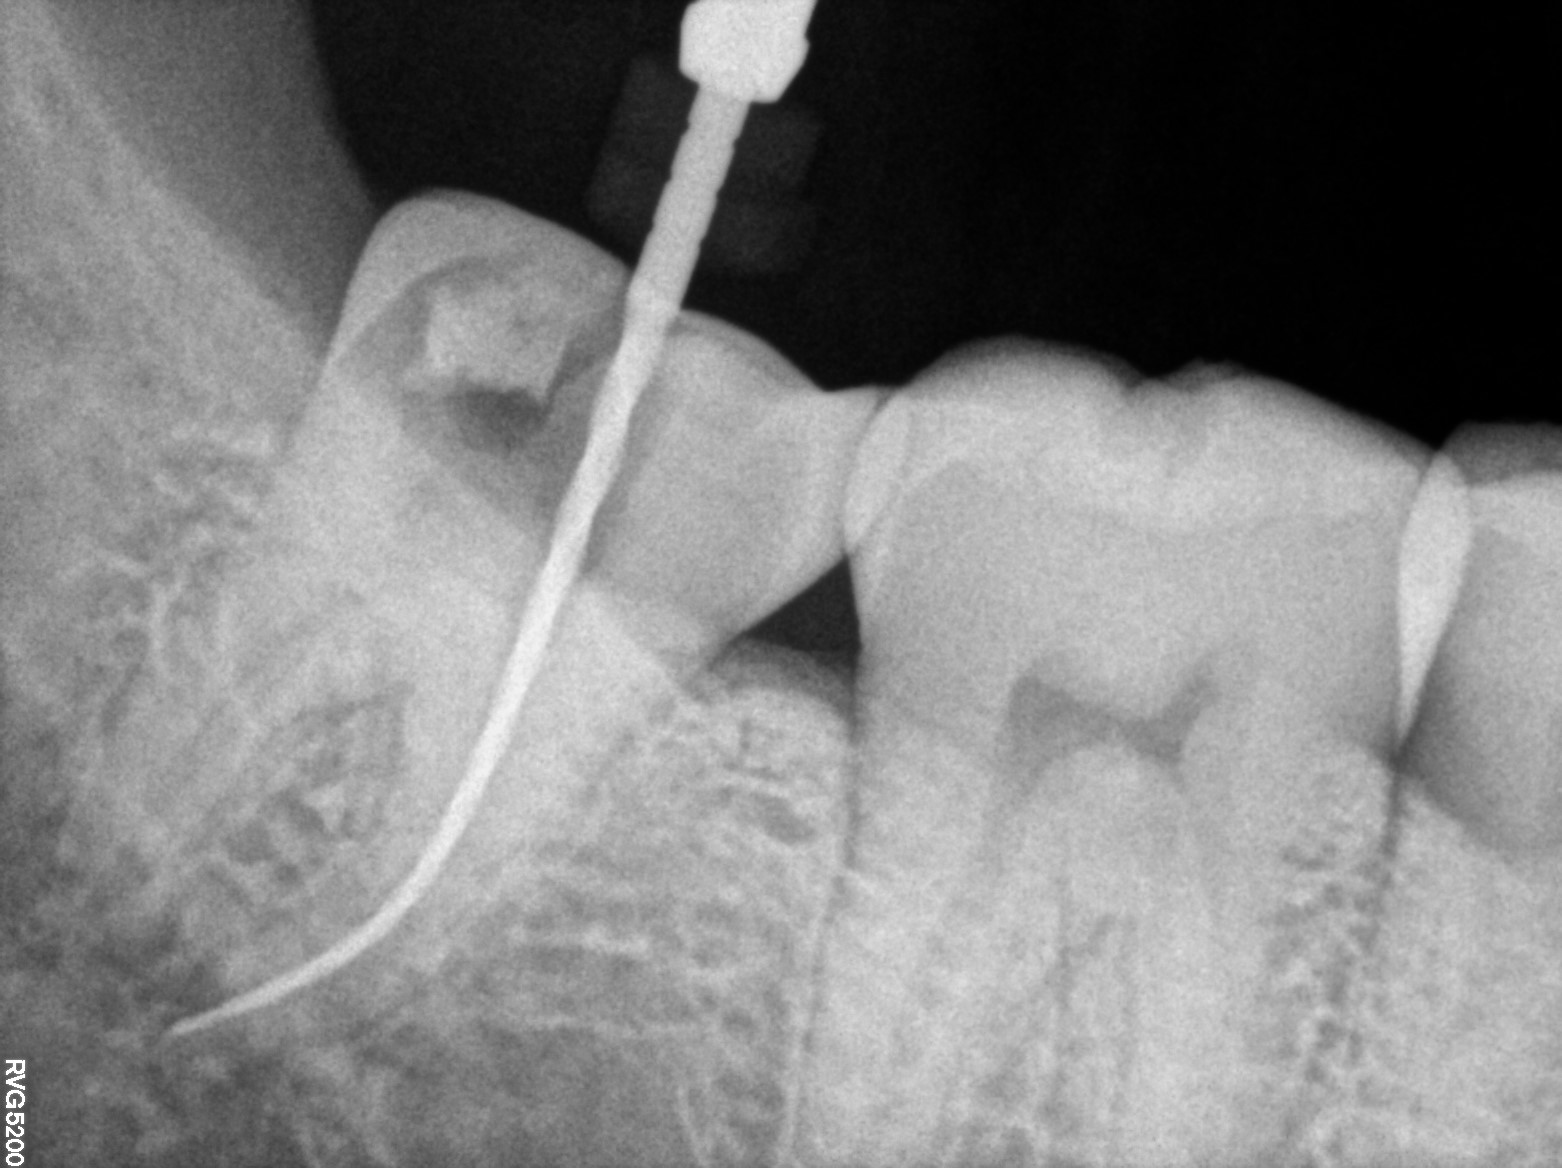

Dental Radiographs FHIR: DocumentReference · LOINC 24641-7

R65.jpg

24641-7